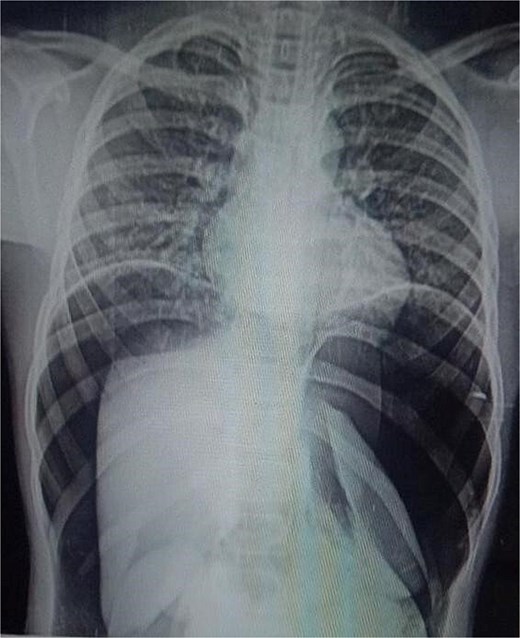

On arrival, he was alert but visibly distressed due to pain. His vital signs were stable initially, but on examination, he had signs of generalized peritonitis with tense, diffusely tender abdomen in all quadrants and absent bowel sounds. Digital rectal examination was unremarkable. Initial laboratory investigations showed a total leukocyte count of 9.3 × 103/μl and platelet count of 143 × 103/μl. A plain abdominal X-ray demonstrated massive pneumoperitoneum (Figs 1 and 2), strongly suggestive of hollow viscus perforation. Based on clinical and radiological findings, a provisional diagnosis of hollow viscus perforation was made.